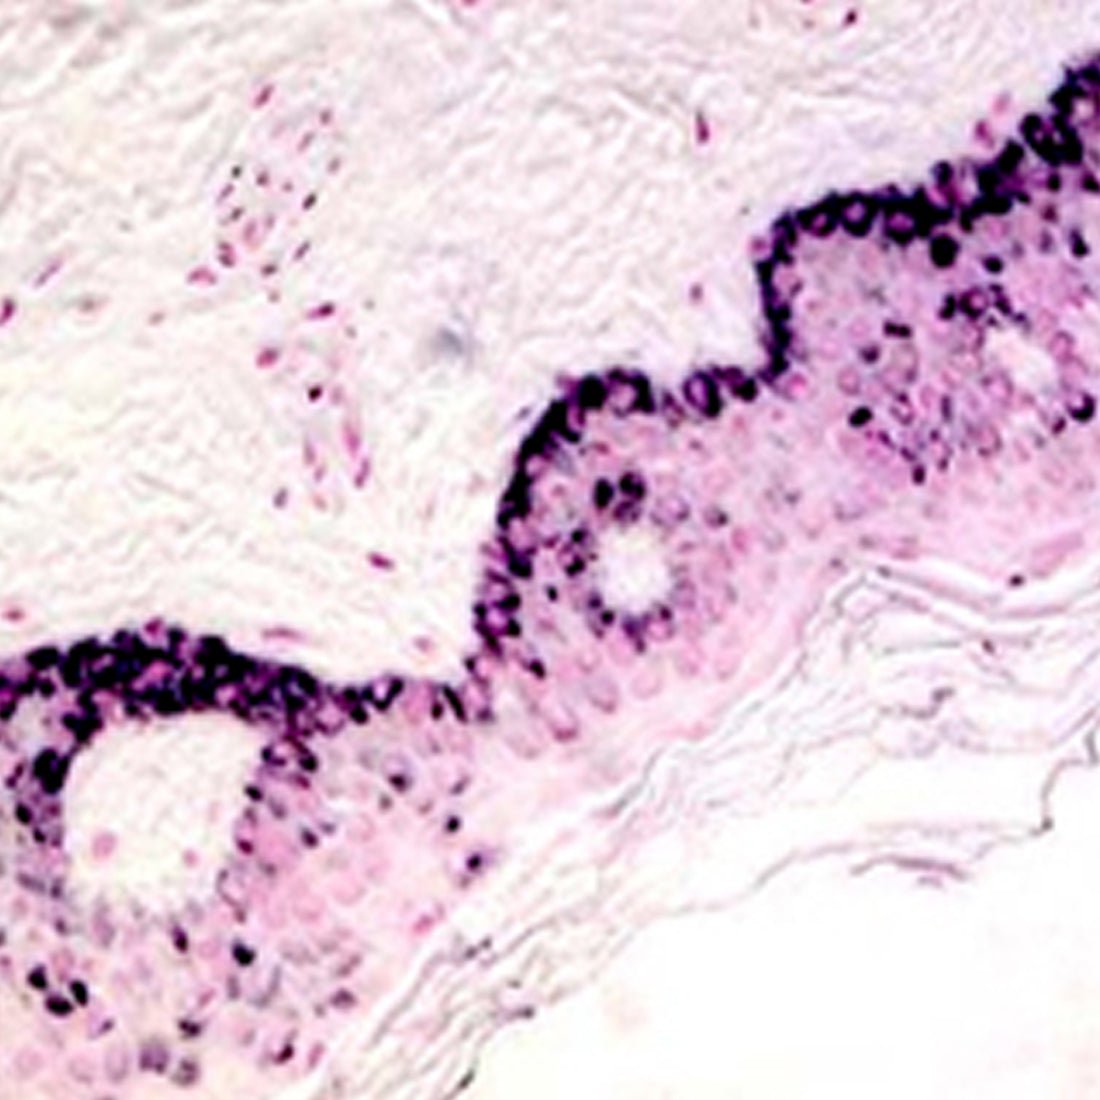

A silver stain intended for use in histological visualization of argentaffin cells and melanin. Our Fontana Masson Stain Kit provides a protocol for conventional or microwave staining. Both procedures yield exceptional results with the microwave option saving valuable time. Argentaffin granules are found in carcinoid tumors and therefore histological visualization can be valuable for diagnosis.

Results:

- Argentaffin Cells- Black

- Melanin- Black

- Nuclei- Pink